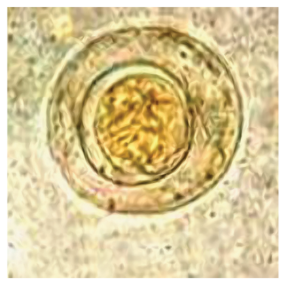

Giardia lamblia (cyst)

knowt flashcard image

83

New cards